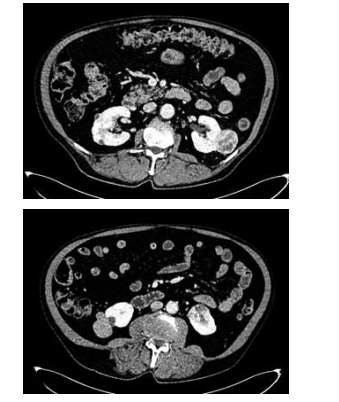

Homem de 65 anos refere hematúria macroscópica há 1 mês. Nega comorbidades ou cirurgias prévias e tem antecedente de cálculos urinários. É tabagista há 40 anos, de um maço por dia. Foi solicitada a tomografia de abdome e pelve, demonstrada a seguir:

Enunciado 4425229-1

(Arquivo pessoal; imagem usada com autorização)

Com essas informações, qual o diagnóstico, uma possível complicação pós-operatória e a medida necessária para reduzir o risco dessa complicação, respectivamente?